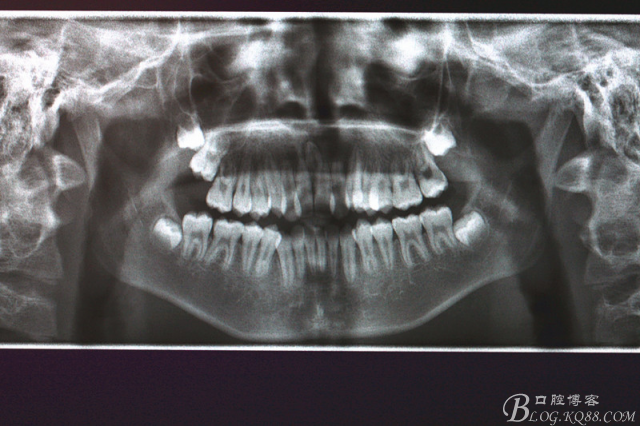

患者:江某某、男、14歲。因正畸治療需要拔除上下頜四顆第一前磨牙。按醫(yī)囑,局麻下拔除四顆第一前磨牙。牙齒拔除后發(fā)現(xiàn)四顆牙齒均為三個(gè)根,頰側(cè)兩根,腭側(cè)一個(gè)根。上頜第一前磨牙偶見三根。下頜第一前磨牙左右兩側(cè)均為三根,實(shí)屬罕見。發(fā)圖片,與同仁共勉。

1.術(shù)前全景片